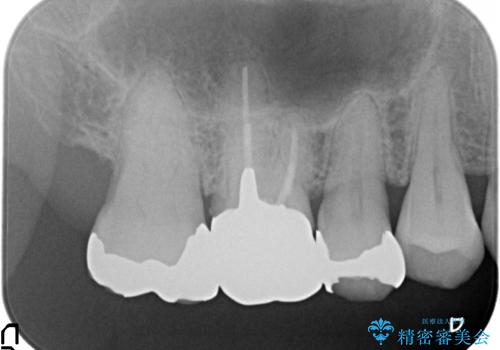

- 右上6番目の銀歯と歯茎の間に隙間ができているのが気になるので診て欲しいといらっしゃった方の症例です。

根管治療も希望されたため、再根管治療終了後、オールセラミッククラウンによる補綴を行いました。